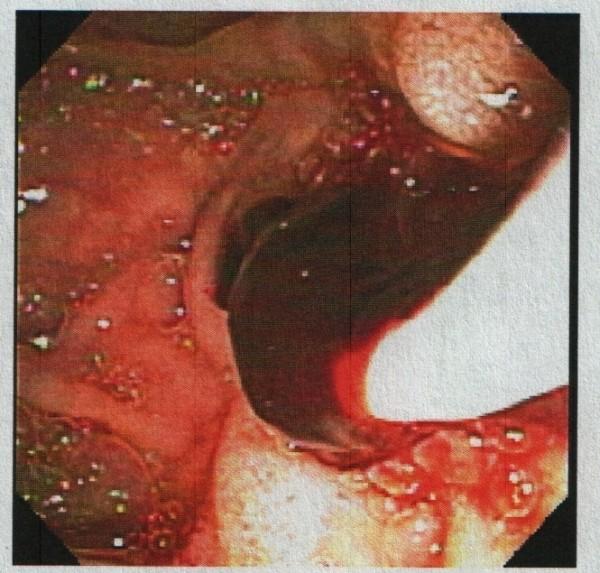

A 91-year-old African-American woman was referred to our out-patient gastroenterology clinic for evaluation of mild epigastric pain and intermittent melena. An abdominal computed tomography scan was remarkable for multiple hepatic cysts. Esophagogastroduodenoscopy revealed multiple blood clots at the ampulla of Vater. Endoscopic retrograde cholangiopancreatography showed a single 18 mm-sized filling defect in the common hepatic duct wall at the junction of the right and left hepatic duct, adjacent to one of the hepatic cysts. The ruptured hepatic cyst communicated to the bile ducts and was the cause of hemobilia with an atypical clinical presentation.

一名91岁的非裔美国女性因轻度上腹部疼痛和间歇性黑便被转诊至我们的门诊胃肠病诊所。腹部计算机断层扫描显示多个肝囊肿。食管胃十二指肠镜检查发现 Vater壶腹有多个血凝块。内镜逆行胰胆管造影显示在左右肝管交界处的肝总管壁上有一个18毫米大小的单一充盈缺损,与其中一个肝囊肿相邻。破裂的肝囊肿与胆管相通,是导致具有非典型临床表现的胆道出血的原因。